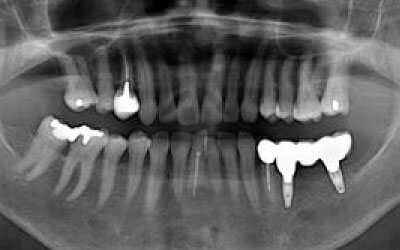

CTでは、骨や歯の状態を3Dで確認でき、正確な距離の測定も行えます。

骨の厚さや傾き、神経の位置などを事前にしっかりと測定することで、安全にインプラントを行うことができます。

骨が薄い場合、そのままインプラントを行うのはお勧めできません。

ただし、事前に骨を増やす治療を行ったり、インプラントと同時に骨を増やす治療を行えば、インプラントは可能です。

ただし、事前にCTで三次元的に神経との距離を測り、治療計画を慎重に立てれば、心配することはありません。